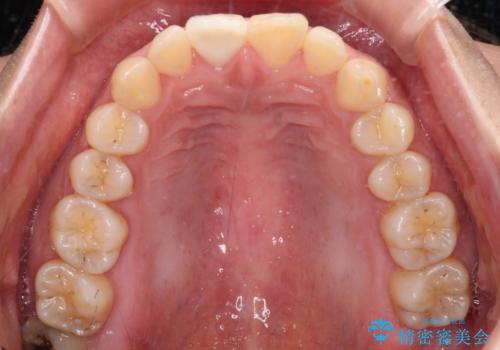

転んで欠けてしまった前歯 オーダーメイドのオールセラミッククラウン

- 転んで欠けてしまった前歯を気にして来院された患者様です。

転んだ際に歯の先端1/4ほどが欠けてしまい、近医にて修復をしてもらったとのことですが、将来的にオールセラミッククラウンを装着する可能性を説明されたため、当院にて補綴治療を行うこととしました。

オーダーメイドタイプのセラミッククラウンは、既製タイプのク色のラウン(スタンダードタイプ)とは異なり、色合いが合うまで何度も修正を行って調整をいたします。